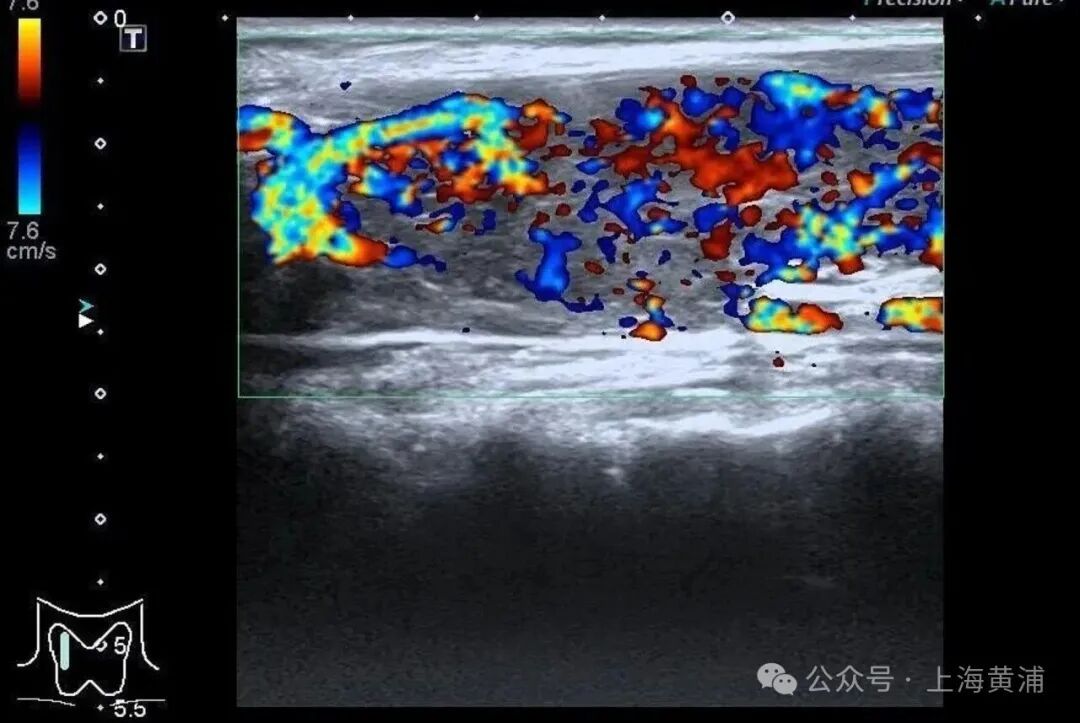

而更致命的隐患藏在她的病史里——陈女士是一位有着20年甲亢病史的患者,并且已经自行停药一年。鉴于病情危重,陈女士被紧急转入瑞金医院卢湾分院内分泌科。

入院后的检查结果显示

陈女士的身体

正被一场“激素风暴”席卷

甲状腺功能检查中,游离T3高达20.83 pmol/L(正常值3.5 - 6.5pmol/L),游离T4高达88.42 pmol/L(正常值11.5 - 22.7pmol/L),这两项核心激素都超过正常上限数倍,而本应调控它们的促甲状腺激素(TSH)却几乎测不出来,这明确证实了陈女士患有极其严重的甲状腺毒症。心脏超声结果同样不容乐观,射血分数仅有40%(正常应高于55%),这意味着心脏泵血能力大幅下降。

同时,CT检查发现她的双侧胸腔、腹腔存在积液。综合各项检查结果,医生判断陈女士患上了甲状腺危象,这是甲亢最凶险的并发症。